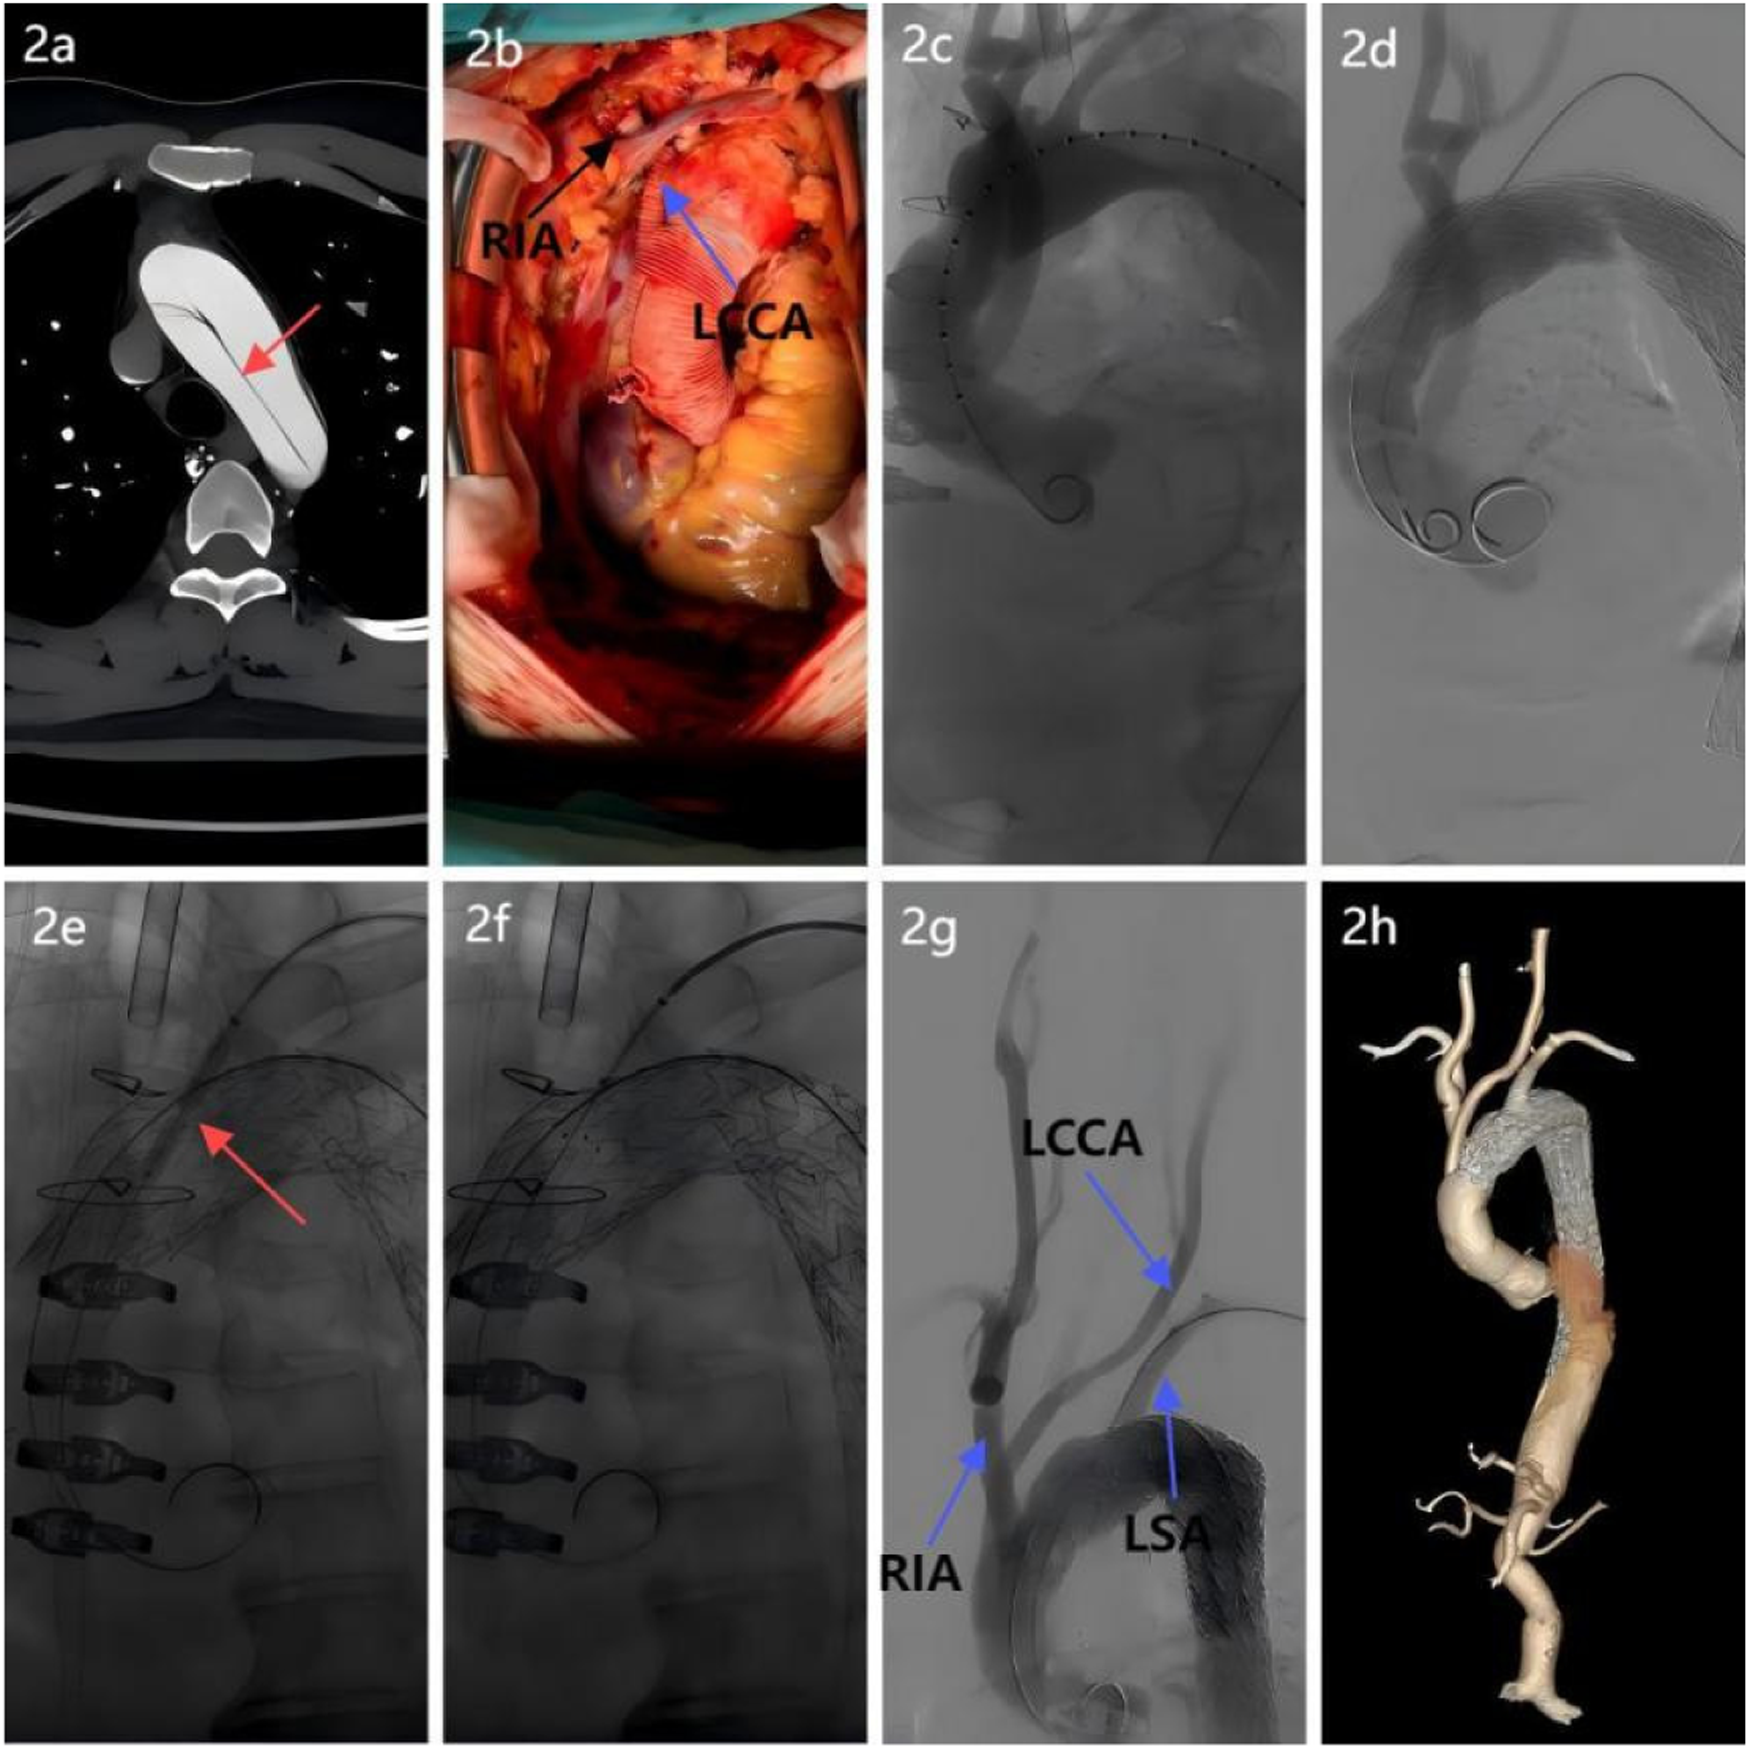

Figure 2

Surgical procedure breakdown. (a) Aortic CTA revealed an aortic arch dissection, necessitating reconstruction of the arch branch vessels; (b) A four-branched prosthetic graft was used: proximal and distal ends were anastomosed end-to-end with the ascending aorta. Two branches were anastomosed to the right innominate artery and left common carotid artery to restore cerebral perfusion; (c) Intraoperative angiography verification confirmed patency of the prosthetic graft and branches, with no anastomotic leaks; (d) A covered stent was implanted distal to the four-branched graft to exclude the false lumen and seal the dissection; (e) After laser fenestration of the left subclavian artery, a balloon was introduced, and balloon dilation revealed a significant notch; (f) A “parachute” technique was used to ensure proper stent apposition; (g) Postprocedural aortography confirmed the patency of all three supra-aortic branches with no evidence of endoleak; (h) Follow-up postoperative CTA of the entire aorta demonstrated patency of the three arch branch vessels, satisfactory stent morphology and position, and absence of endoleak.